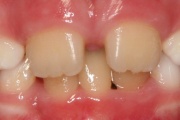

Vali sind huvitav pilt ja me näitame sellega seotud haigust ja sümptomeid